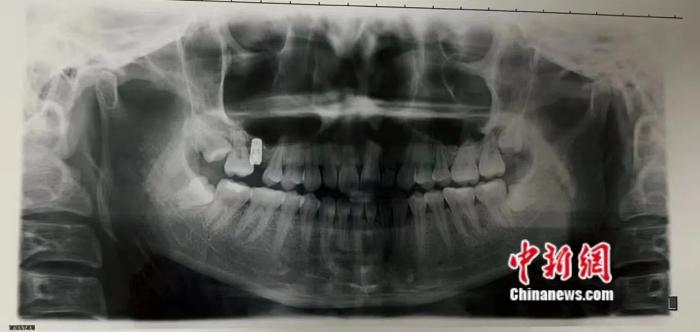

图为今年7月,李婷去一家三甲医院重新检查牙齿所获取的影像受访者供图